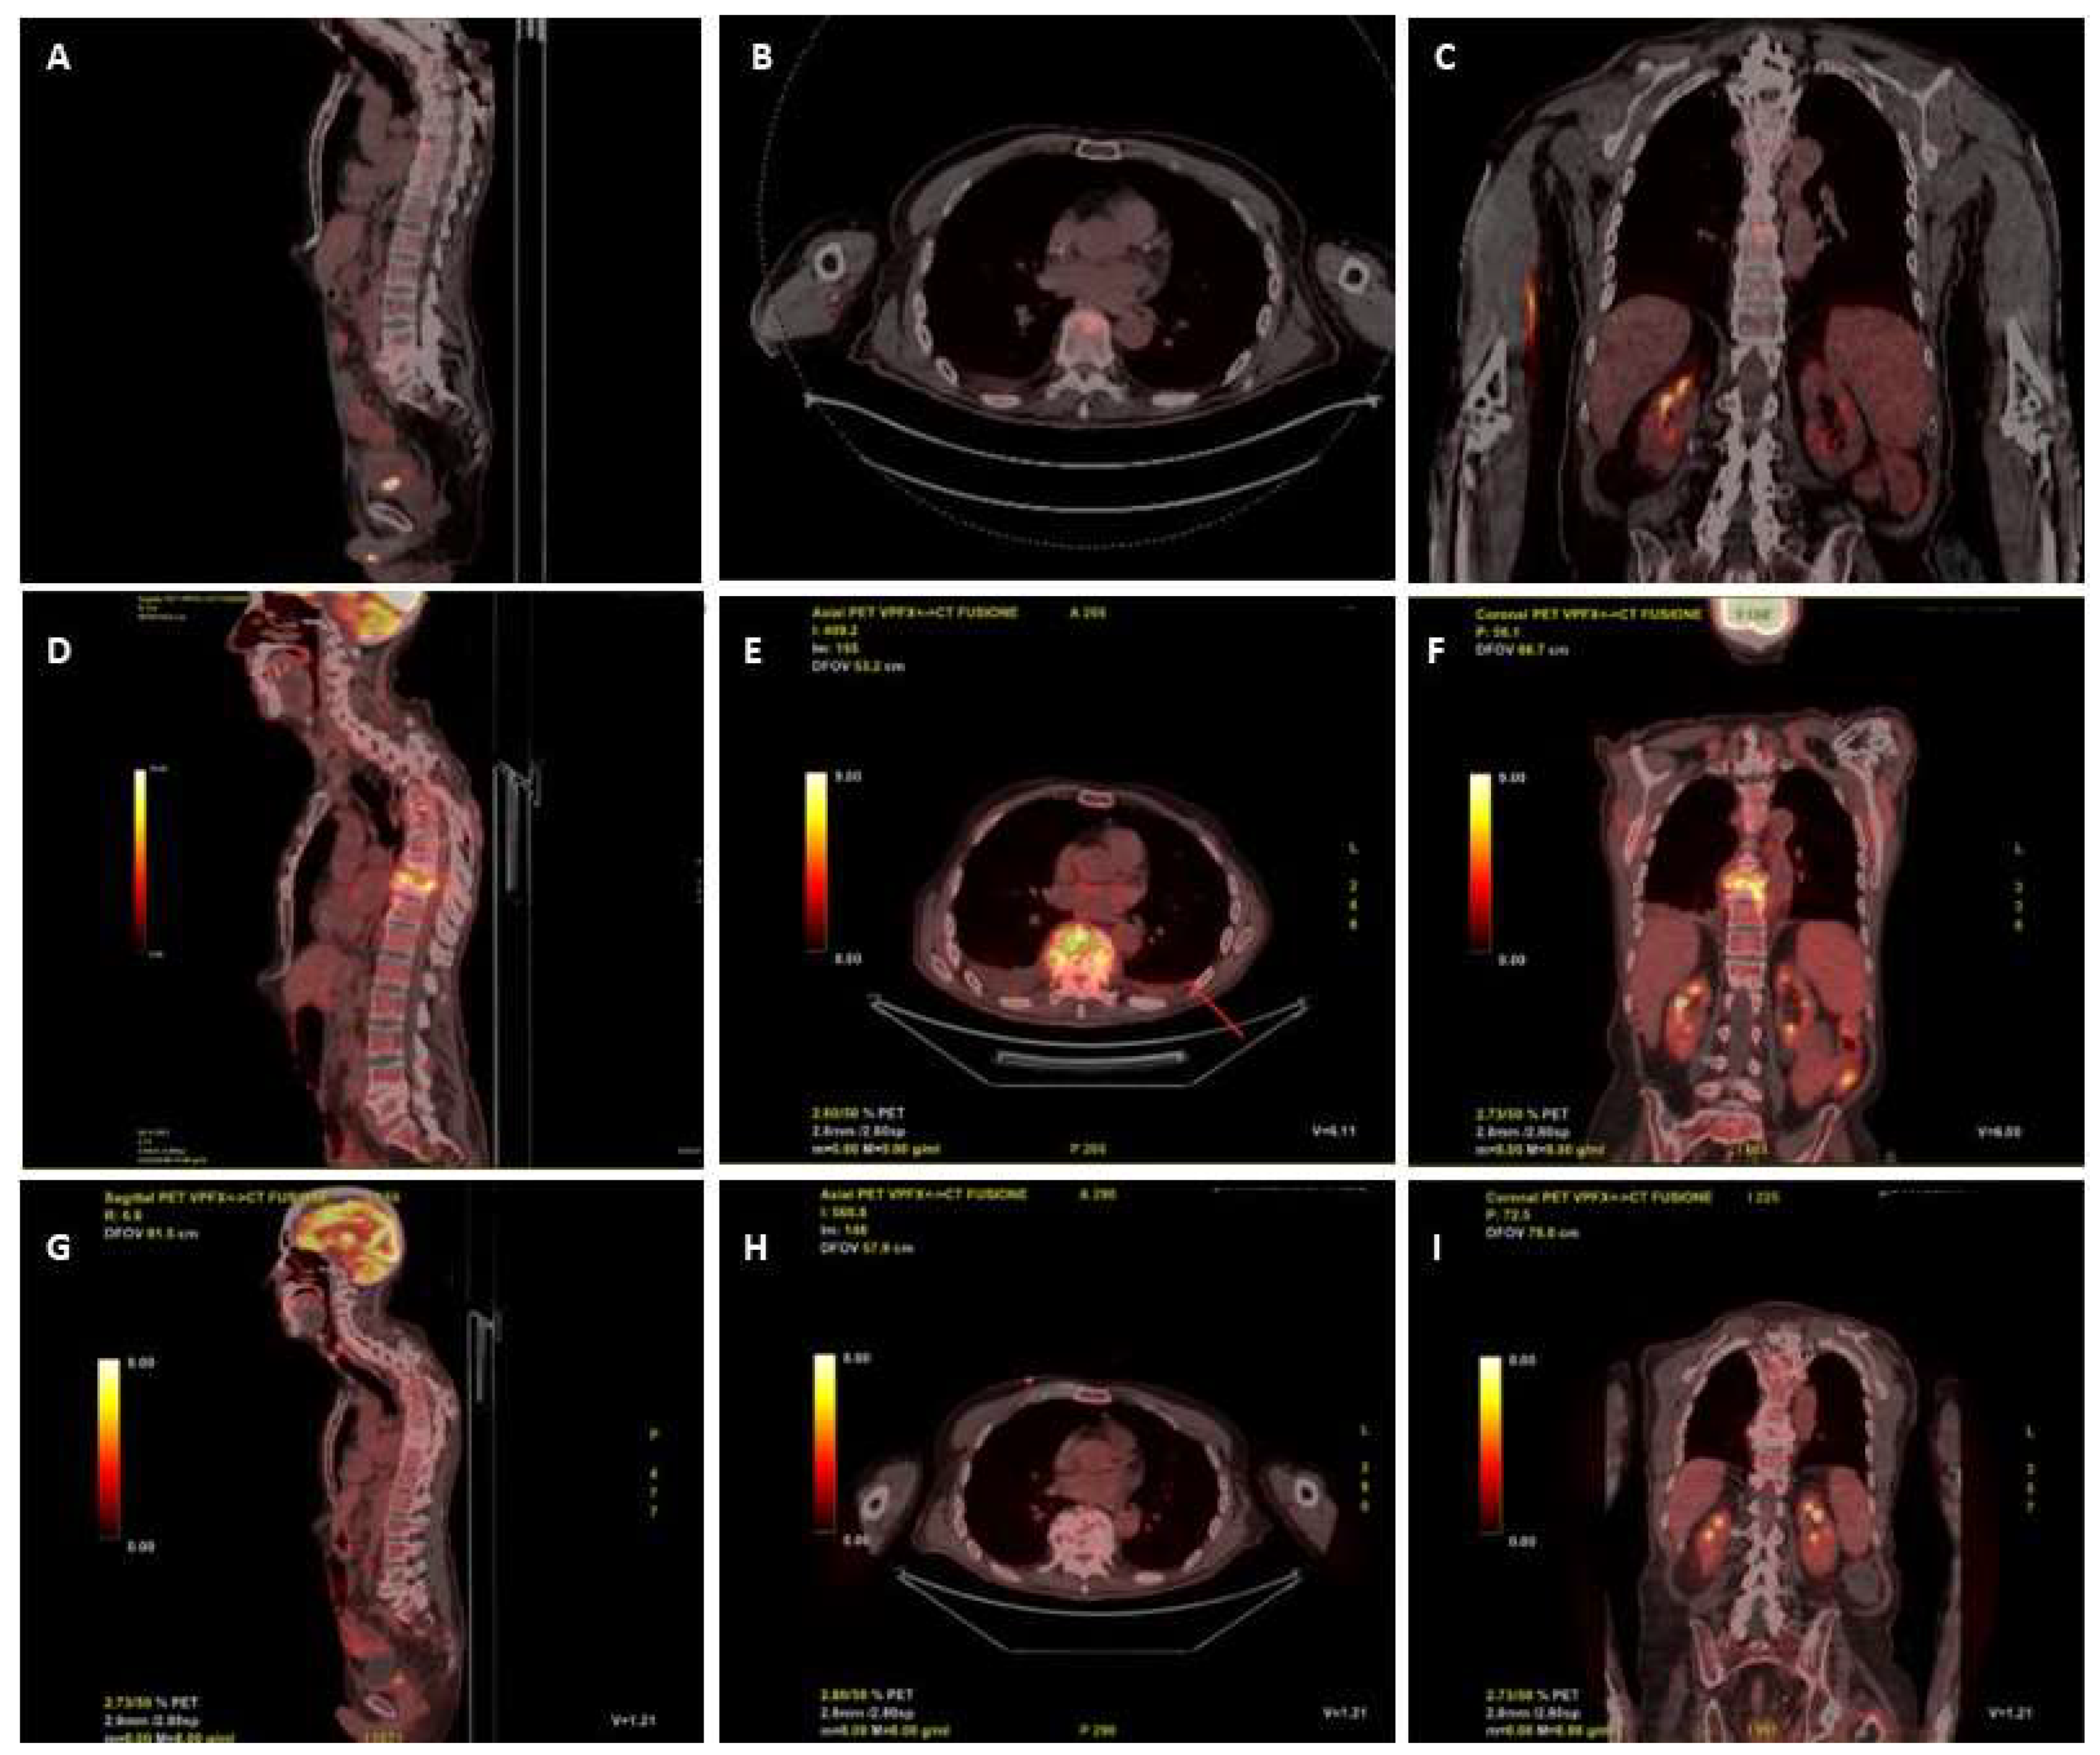

2. Case Report